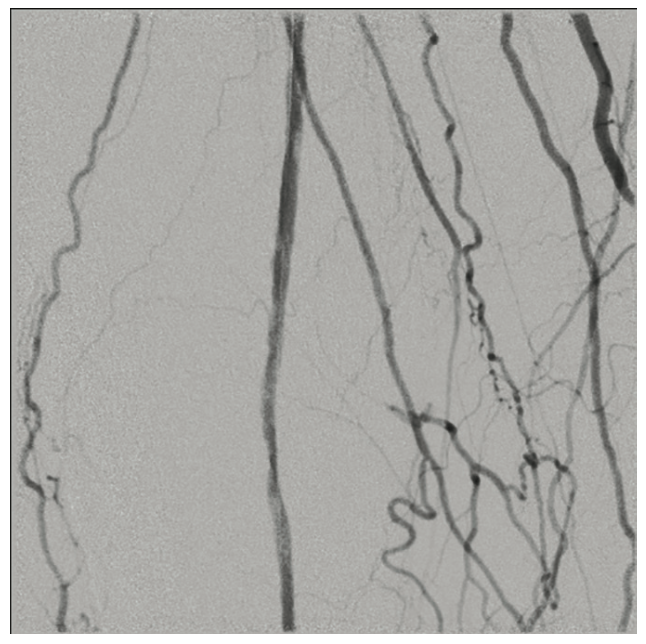

A 6 French (Fr) sheath was inserted into the right femoral artery in an antegrade fashion. An .035-inch x 90 cm Trailblazer (Medtronic) was inserted over an .035-inch x 180 cm Aquatrack guidewire (Cordis, A Cardinal Health company) and advanced into the right popliteal artery. Angiography was performed prior to surgical cut down of the posterior tibial artery (PT) (Figure 1). Access into the PT was made using a 4 Fr micropuncture pedal sheath (Cook Medical). An .014-inch Confianza guidewire (Asahi Intecc) was inserted and advanced into the PT. Using the stiff Confianza, a Viance Flexible CTO catheter (Medtronic) was advanced. When Viance extravasated from the PT, an Aquatrack wire and .035-inch Trailblazer were introduced and advanced in a antegrade manner. The Viance and Trailblazer could be visualized going in different directions (Figure 2). Using that image, the Viance was pulled back and repositioned to find the true lumen from the bottom to the top, using the guidance from the wire. The Confianza was readvanced after the true lumen was found, and Aquatrack was pulled back into the Trailblazer and eventually removed. The Confianza wire was advanced further into the .035-inch Trailblazer, and eventually pulled through the right femoral artery sheath in a retrograde fashion (Figure 3). The right femoral artery Trailblazer was removed. A TurboHawk SX-C atherectomy catheter (Medtronic) was used to debulk the plaque and achieve luminal gain from the popliteal artery into the tibioperoneal trunk (Figure 4). Drug-coated balloon angioplasty was performed using the IN.PACT balloon (Medtronic) into the popliteal artery (Figure 5). The TurboHawk was reinserted and advanced further down to the peroneal artery into the tibioperoneal trunk in order to establish luminal gain in the distal vessel. Final angiography revealed successful recanalization of the lower extremity vessels through the use of the antegrade/retrograde method, with distal access through the posterior tibial artery (Figure 6).